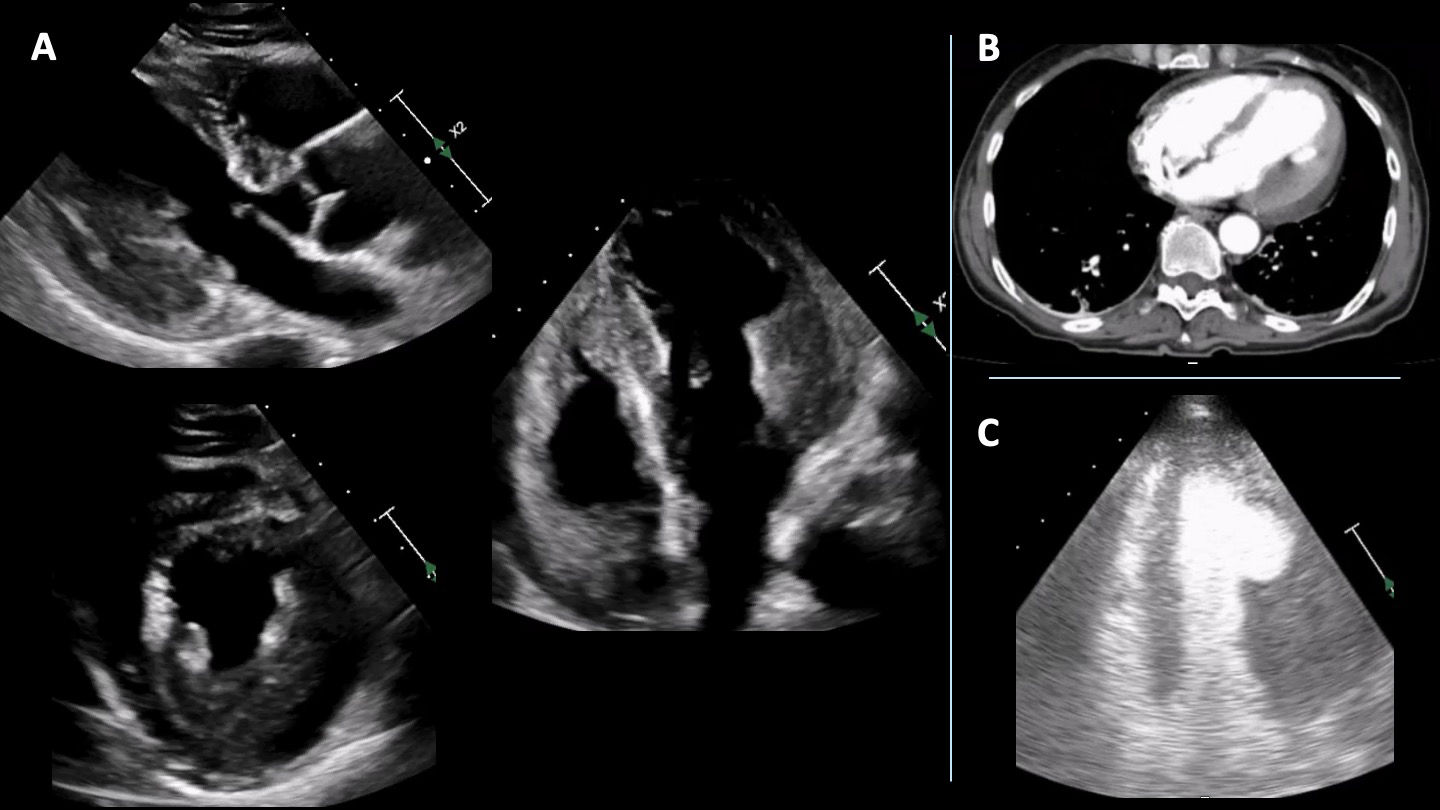

Follow-up TTE at 13 days showed a significant reduction in the thickness of the mid-basal segments of the left ventricular lateral and posterior walls (now measuring 16 mm), along with an image suggestive of a left ventricular thrombus (Figure 3A). The patient was discharged on corticosteroids, azathioprine, and anticoagulation. At six-month follow-up, she remained asymptomatic. CMR showed asymmetric wall thickening in the basal segments of the anterior septal, anterior, lateral, and posterior walls, although less pronounced (13 mm) (Figure 3B). There was no evidence of active inflammation, and LGE was observed in the subepicardial region of the basal posterior wall, consistent with sequelae of acute myocarditis (Figure 3C and D). No intraventricular thrombus was identified. The patient remains on low-dose prednisolone without evidence of clinical relapse.

Imaging assessment following initiation of immunosuppressive therapy. (A) Echocardiogram performed 13 days later showing localized wall thickness reduction. (B) Cardiac magnetic resonance (CMR) imaging in four-chamber view, performed 6 months later, showing mild hypertrophy in the basal segment of the lateral wall of the left ventricle. (C) T2-weighted CMR sequence showing no evidence of myocardial oedema. (D) CMR showing subepicardial/mid-wall late gadolinium enhancement with linear distribution in the basal segment of the posterior wall.